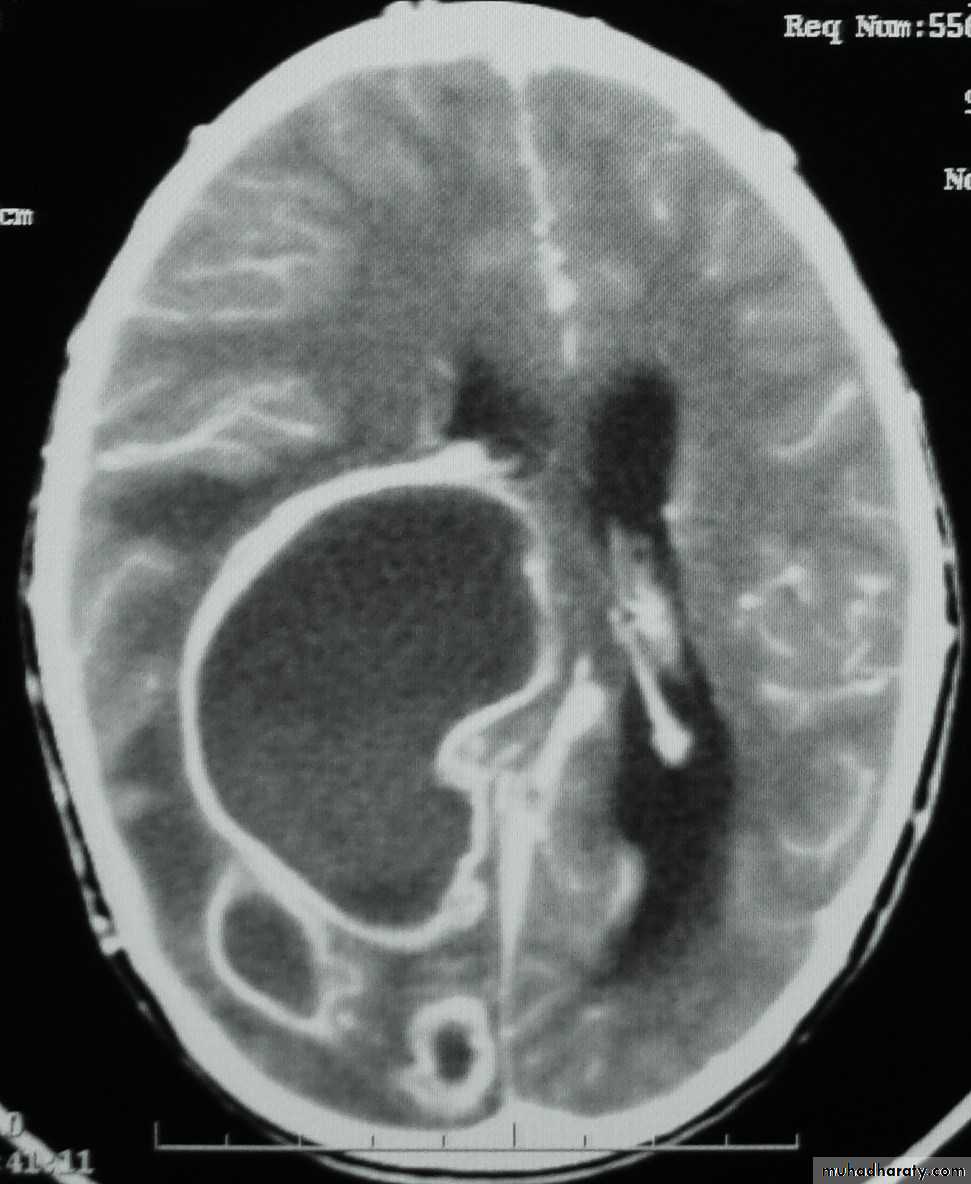

Brain Abscess CT with contrast

Neurosurgery

• They will show a single (or multiple) space occupying lesion that is well delineated with an enhancing wall, with variable surrounding oedema.